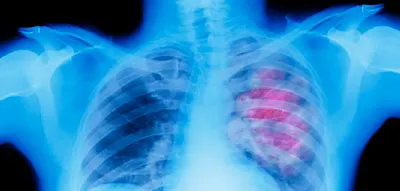

Nach einer Rheuma-Diagnose fürchtete unser Autor, lebenslang auf Spritzen angewiesen zu sein. Längst braucht er sie nicht mehr. Welche Rolle spielt sein radikales Umdenken? Stern plus